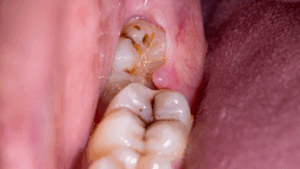

Wisdom Teeth Causes Infection and Swelling:

Partially erupted wisdom teeth can create pockets where bacteria accumulate, leading to infections and gum inflammation. This condition, known as pericoronitis, can cause significant discomfort and swelling.

Wisdom Teeth Causes Teeth Decay and Gum Disease:

Wisdom teeth are located at the back of the mouth, making them harder to clean thoroughly. This difficulty can increase the risk of cavities and gum disease, which can affect overall oral health.